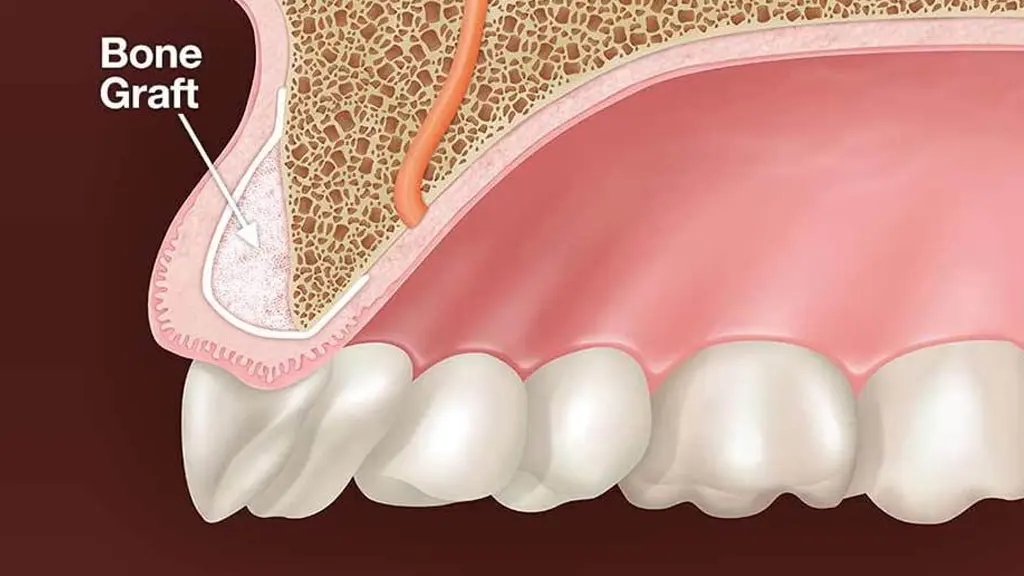

- بدون برش لثه (در برخی موارد): با استفاده از راهنمای جراحی دیجیتال، بسیاری از مراحل بدون نیاز به جراحی باز انجام میشوند.

- کاشت ایمپلنت با حداقل تهاجم

به دلیل استفاده از راهنمای جراحی دیجیتال، مراحل کاشت بسیار سریعتر و کمتهاجمیتر انجام میگیرند. - بدون نیاز به بخیه در بسیاری از موارد

در این روش، برش لثه به حداقل رسیده یا کاملاً حذف میشود که باعث کاهش درد، خونریزی و تورم میگردد. - زیبایی طبیعی و هماهنگ با لبخند شما

- ساخت گاید جراحی (راهنمای دقیق برای کاشت)

- کاشت ایمپلنت با دقت میلیمتری و حداقل تهاجم